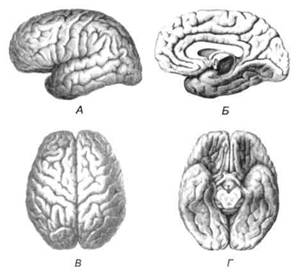

Передний мозг состоит из двух полушарий, покрытых серым веществом — корой (ее толщина у взрослого человека колеблется от 1 до 5 мм). При рас-

Рис. 13. Латеральная (А), медиальная (Б), конвекситальная (В) и базальная (Г) поверхности больших полушарий

смотрении поверхности мозга и для локализации отдельных участков в нейропсихологии принято пользоваться специальной терминологией, обозначающей плоскость или сектор обзора, на которых фиксируется внимание. Кон-векситальный (букв. — выпуклый, здесь — наружный) мозг — поверхность полушарий, видная при-взгляде сверху; базальный мозг — поверхность и анатомические структуры, видные при взгляде снизу; латеральный мозг — поверхности, видные при взгляде сбоку; медиальный мозг— поверхности полушарий, обращенные внутрь продольной щели мозга (рис. 13).

Поверхность полушарий покрыта бороздами и извилинами, причем величина и форма борозд подвержены значительным индивидуальным колебаниям, вследствие чего не только мозг различных людей, ной полушария одного и того же индивида по рисунку борозд могут заметно отличаться друг от друга (рис. 15). Глубокими постоянными бороздами пользуются для разделения каждого полушария на большие участки, называемые долями. Такими бороздами являются боковая (сильвиева) борозда, центральная (роландова) борозда и те-менно-затылочная борозда, отчетливо обозначенная лишь на поверхности продольной шели мозга, делящей его на два полушария (рис. 16). Основные извилины показаны на рис. 17.